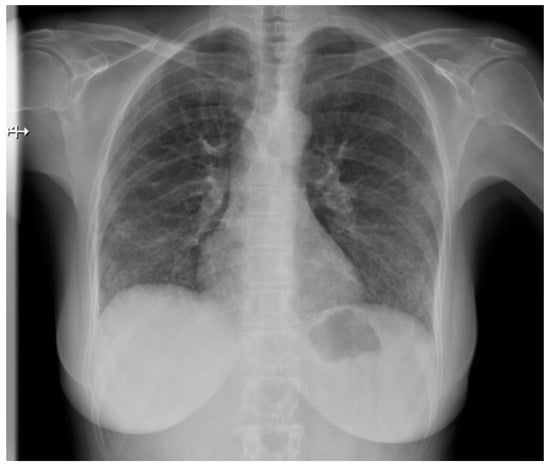

Pulmonary fibrosis (Figure 3) might be observed on a chest X-ray only in patients in an advanced stage, thus largely diminishing the role of classical radiology in the diagnosis of pulmonary involvement in SSc patients [21].

Figure 3.

P-A view of the chest radiograph in a patient with systemic sclerosis demonstrates moderate pulmonary fibrosis.